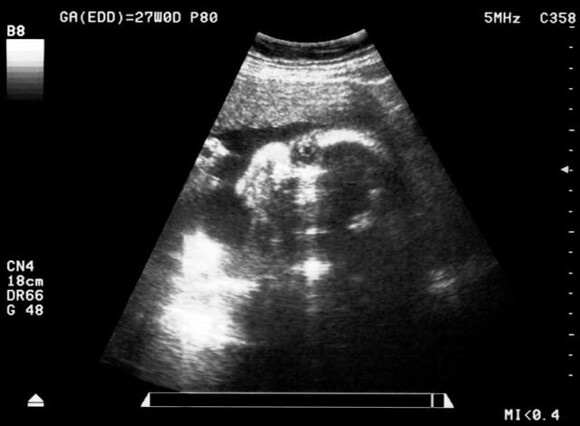

พัฒนาการทารกในครรภ์สัปดาห์ที่ 25-28

“หนูลืมตาและหลับตาได้แล้ว”

- ทารกมีความยาวประมาณ 30 - 35 เซนติเมตร

- ทารกมีน้ำหนักประมาณ 600 - 1,000 กรัม

- ผิวทารกมีรอยย่น เริ่มมีไขมันใต้ผิวหนัง

- ศีรษะโต มีขนคิ้วและขนตา

- สามารถลืมตาและหลับตาได้แล้ว

- สามารถได้ยินเสียงจากภายนอก

- สะอึกได้